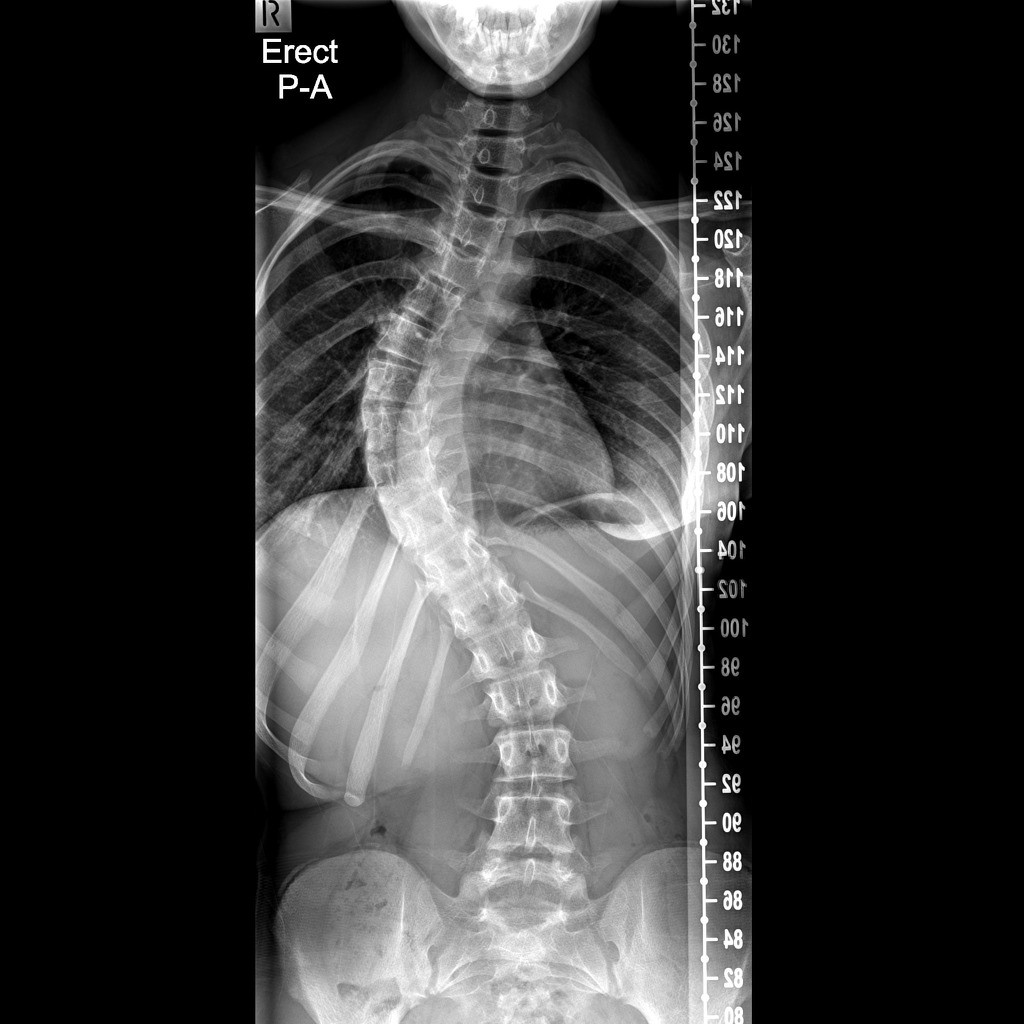

Başın bir tarafa doğru eğimli olması, göğüs kafesinde asimetri, kürek kemiklerinden birinin diğerine göre daha tümsek şeklinde olması, kalçalar ve omuz seviyeleri eşit olmaması, bacak eşitliklerinin aynı olmadığından şikayet edilmesi gibi durumlar skolyoz habercisi olabileceğinin beliren Prof. Dr. Bahadır, “Skolyozun ilerleyişi kişinin yaşı, cinsiyeti, eğriliğin tipi ve büyüklüğüyle farklılık gösterir. Skolyoz kız çocuklarında daha fazla görülmektedir. Hızlı büyümenin olduğu ergenlikte eğrilik hızlı ilerler. Skolyozun tanısı için dikkatli bir muayene ve basit bir röntgen filmi yeterlidir. Yalnız her eğrilik skolyoz değildir. Skolyozda vertebra eğimi 10 derecenin üzerinde olmaldır. Bunun altındaki eğrilikler skolyoz olarak sınıflandırılmaz” şeklinde konuştu.